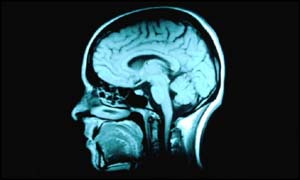

The scientists scanned the brains of patients

They carried out brain scans on 21 men with sleep apnoea and 21 men without the condition.

The scans revealed that men with sleep apnoea had significantly fewer brain cells in areas of the brain that control speech, movement and emotion.